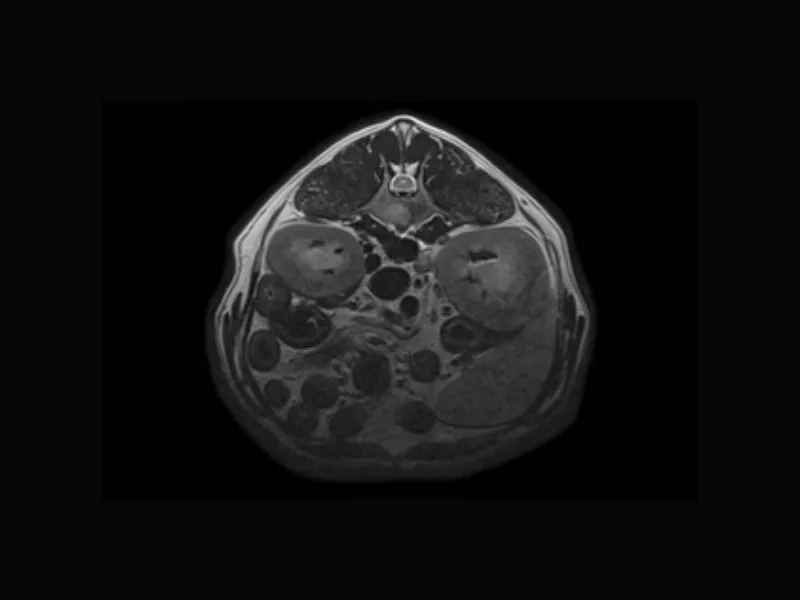

Supreme vet-mr – T2W of canine abdomen with respitarory gating